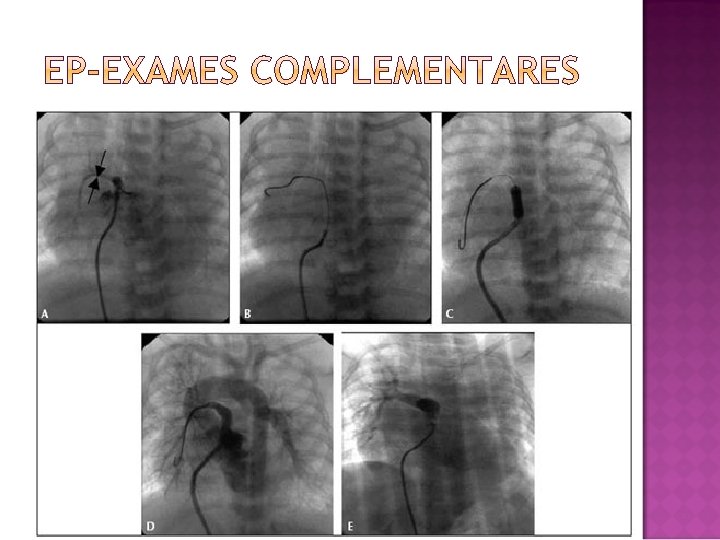

Foi submetida ao cateterismo cardíaco. Apresentou 02 PCR durante o procedimento. Êxito nas manobras de reanimação. Sat de O 2 inicial= 30% Sat de O 2 final= 96% Retorna ao HRAS estável hemodinamicamente.

Insuficiência tricúspide acentuada. Valva pulmonar espessada. VE com tamanho e contratilidade espessada. Aorta sem alterações, não visualizado canal arterial. Realizada dilatação valvar pulmonar com cateter balão sequencial: B. Maverick, B. Ultrasoft e finalmente Profiler. Gradiente final VD-TP 10 mm. Hg. Não observamos IP signifativa residual e manteve IT acentuada igual a condição inicial. Saturação de O 2 inicial de 30% e Sat final= 96%.